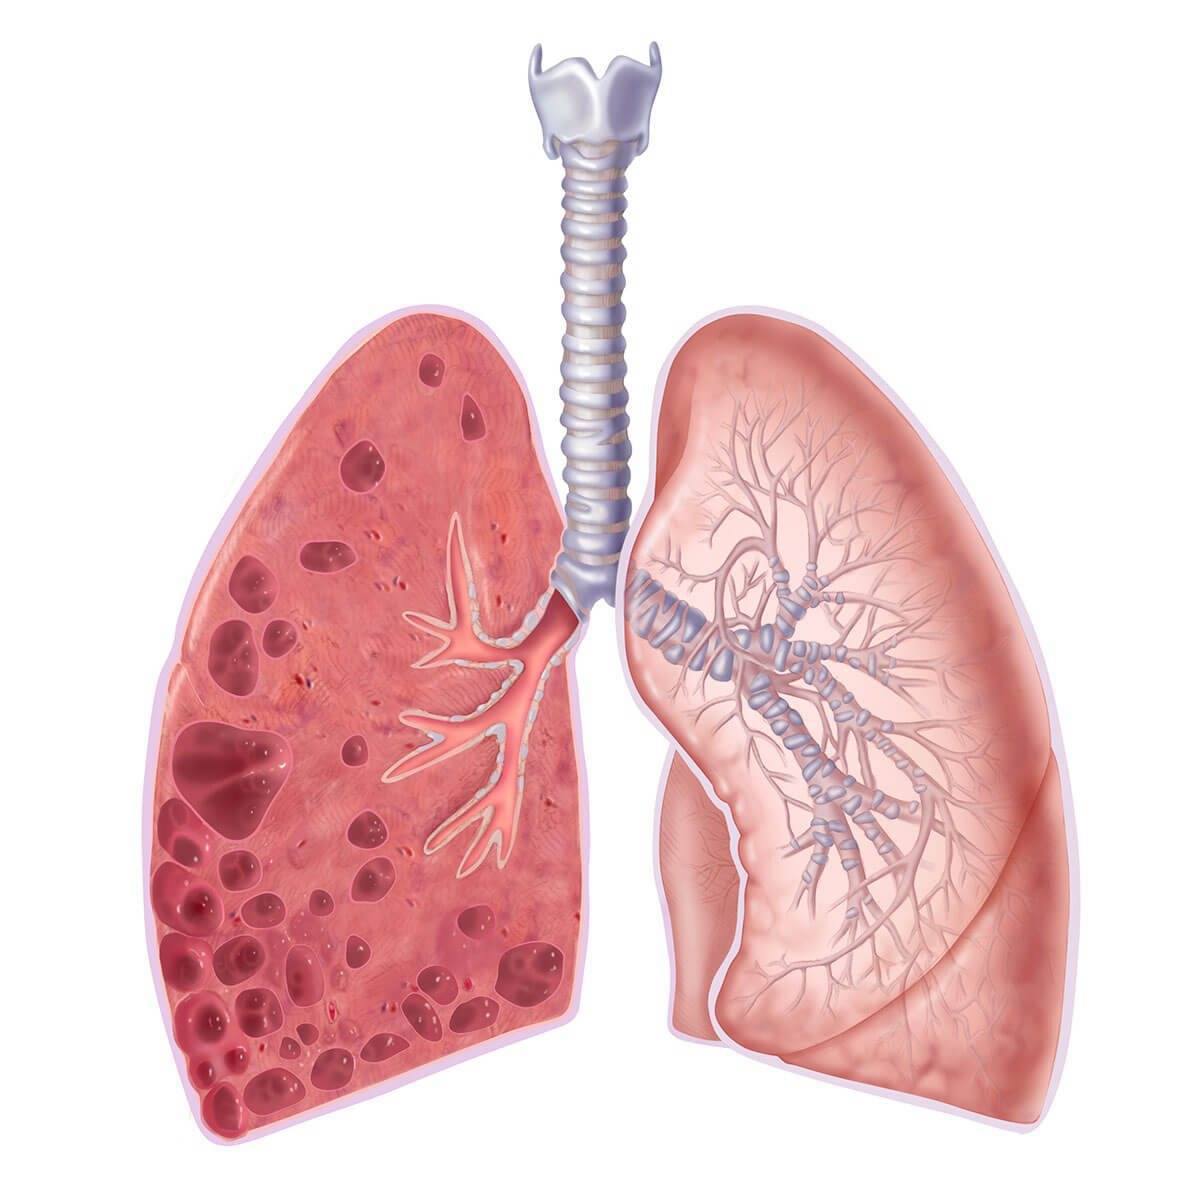

Рентгеновские снимки при врожденной эмфиземе легкого

Раздел: Визуальные уроки